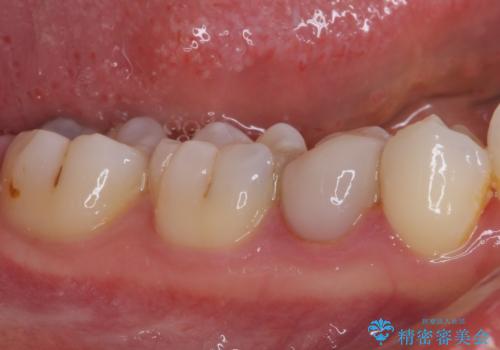

- 神経を抜く処置の後に装着したプラスチックのクラウンが外れてしまったとのことで来院された患者様です。

患者様自身、神経の取り除かれた歯はしっかりと製作されたクラウンを装着するべきと理解していただいていたため、オールセラミッククラウンにて補綴治療することとしました。

丈夫なクラウンを装着できただけでなく、形態や色調も自然に仕上げることができました。